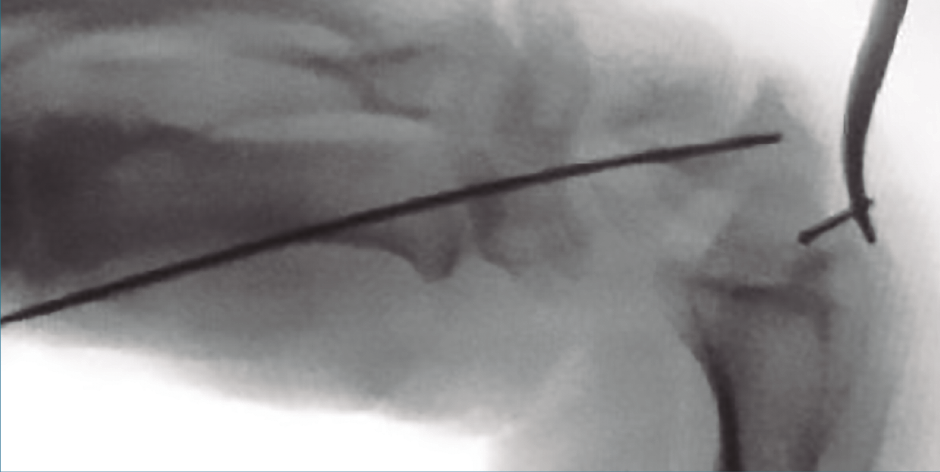

Esta técnica fue descrita en 2001 por Slade(31). Lo primero que debemos realizar es un control escópico del escafoides que nos permitirá descartar otras lesiones. Se debe localizar el eje central del escafoides, que se verá mejor pronando y flexionando la muñeca. Una vez realizado, debemos colocar una aguja de Kirschner siguiendo el eje del escafoides; puede realizarse de forma percutánea, con un alto índice de lesiones tendinosas, sobre todo del extensor pollicis longus, o mediante un miniabordaje dorsal, que es la técnica que preferimos, distal al tubérculo de Lister, con una artrotomía longitudinal, para localizar el polo proximal del escafoides.

Este tipo de síntesis estaría indicada en fracturas del polo proximal y en fracturas del tercio medio.

Una vez colocada la aguja de Kirschner en el centro del escafoides, en fracturas estables las podemos recuperar por volar y radial a nivel del pulgar, lo que nos permitirá una extensión de muñeca para realizar un correcto control escópico. En fracturas inestables podemos usar la aguja de Kirschner a modo de joystick para reducir la fractura. Al realizar la medición debemos restar 4 mm, ya que el tornillo debe quedar totalmente enterrado en el polo proximal y no invadir la articulación escafotrapeciotrapezoidea.